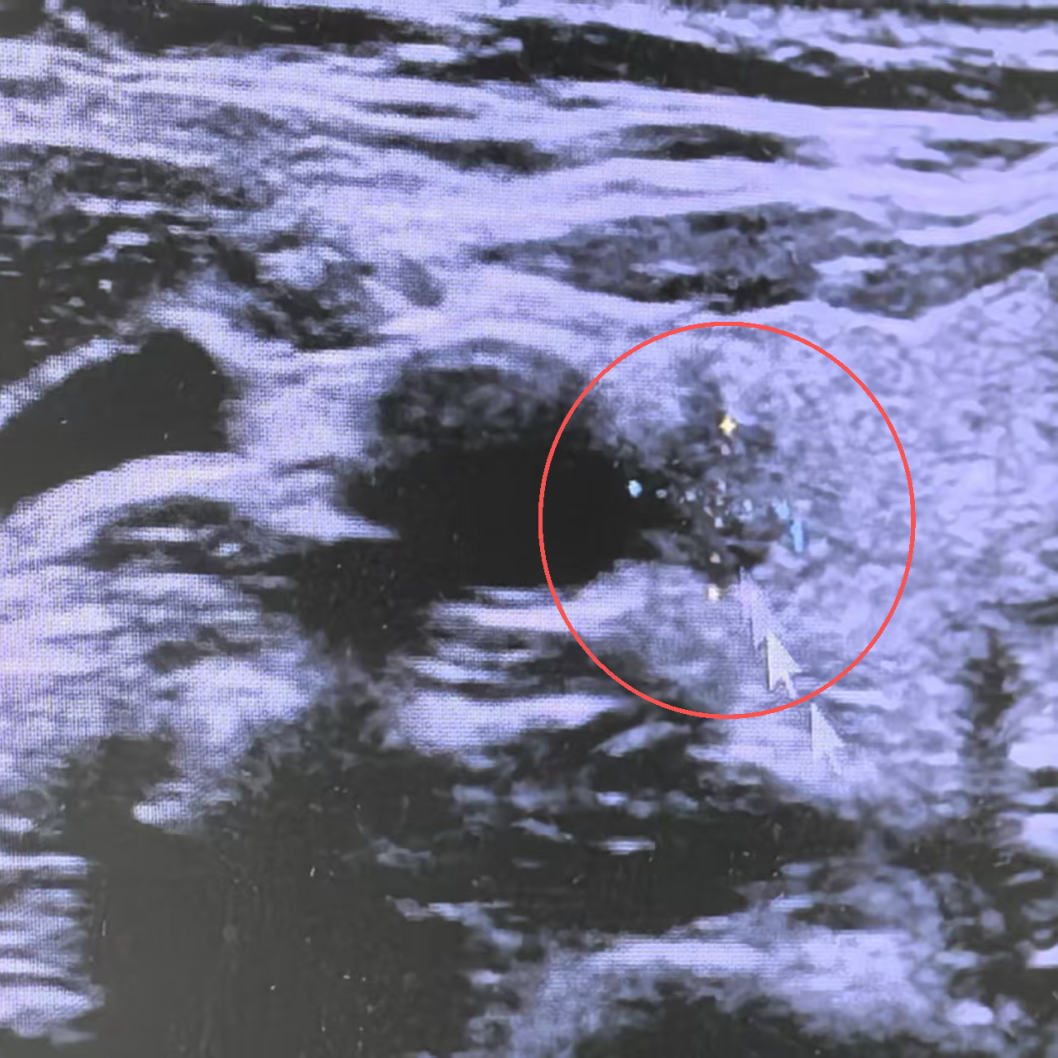

结果显示:甲状腺左侧叶可见直径3.5厘米的实性低回声结节,形态不规则、边界不清,被归为 C-TIRADS 4c级(这种分级对应的恶性风险在 50%-90% 之间);

甲状腺右侧叶发现4a级可疑结节,同时左侧颈淋巴结还出现疑似转移迹象。

随后通过超声引导下细针穿刺、免疫组化检测、分子学检测这“三位一体”的检查,张姐最终确诊为“甲状腺乳头状癌并淋巴结转移”,需尽快手术治疗。这个结果让全家都很困惑:不是都说甲状腺结节、甲状腺癌是“气出来的”?